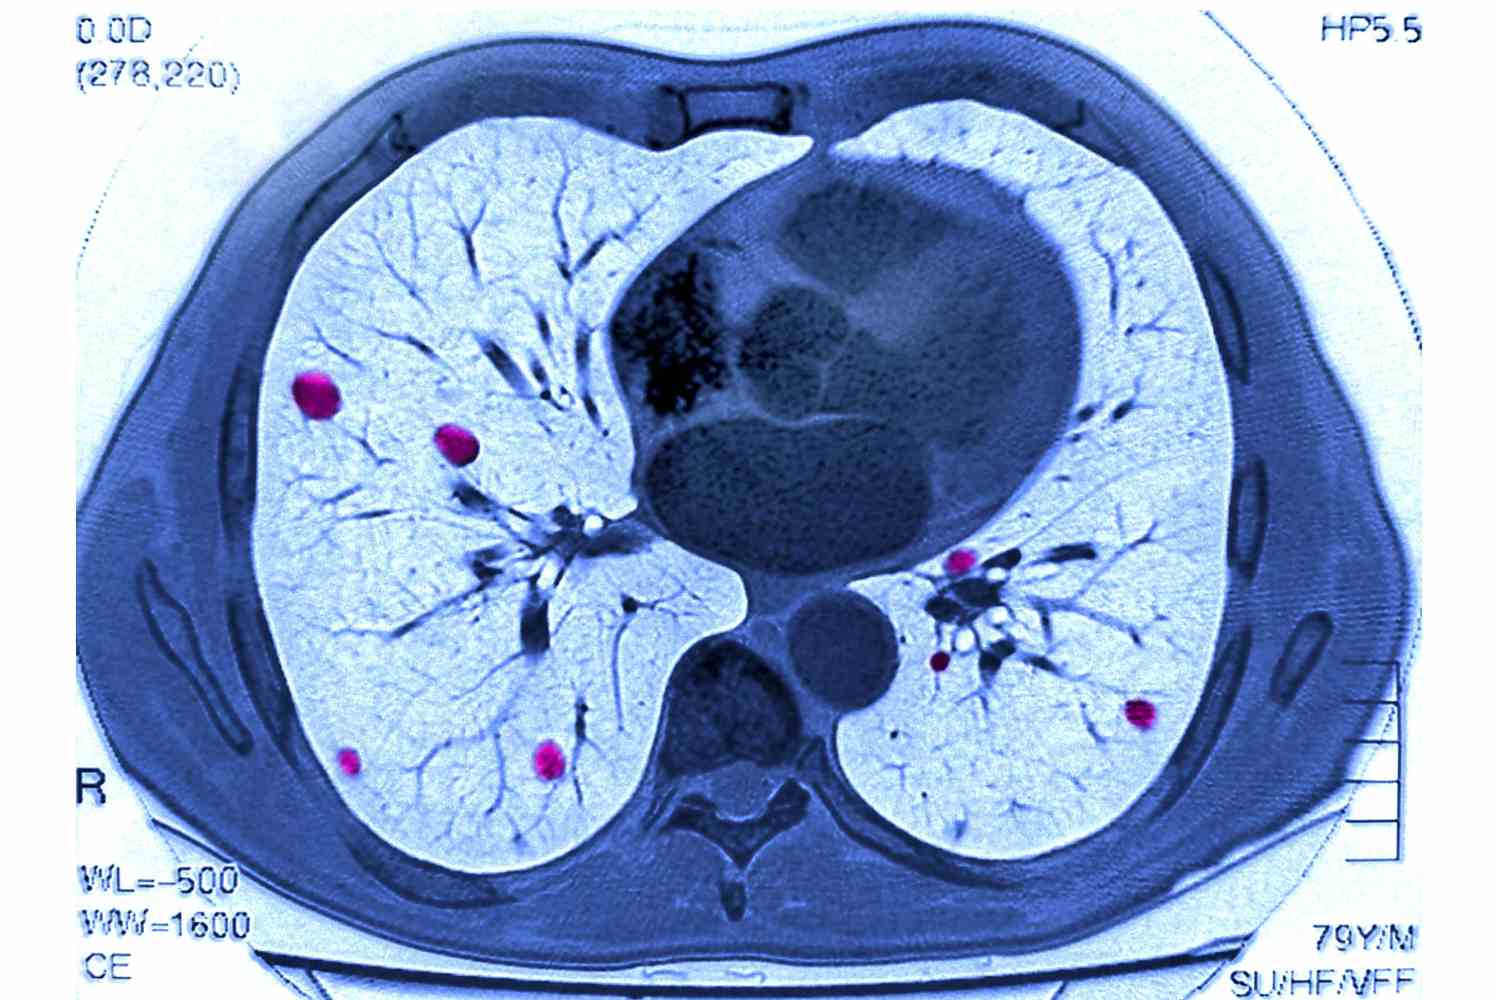

Quando o RX não esclarece completamente o quadro clínico ou há suspeita de complicações, a TC de alta resolução (TCAR) entra em cena. Ela permite observar com riqueza detalhes como espessamento septal, opacidades em vidro fosco, nódulos pulmonares, destruição alveolar e alterações brônquicas.

Com cortes finos e reconstruções multiplanares, é o exame de escolha para avaliar a extensão de uma fibrose, o padrão intersticial, ou confirmar/emergir lesões compatíveis com sequelas da COVID-19. Também auxilia no estadiamento de neoplasias pulmonares e investigações vasculares (angio-TC).

O técnico deve dominar as posições ideais de RX (PA e perfil), saber realizar TC com protocolo de alta resolução, entender a diferença entre reconstruções axiais e coronais e seguir normas de proteção radiológica. Em muitos serviços, é ele quem realiza os exames e garante a qualidade das imagens entregues ao radiologista.